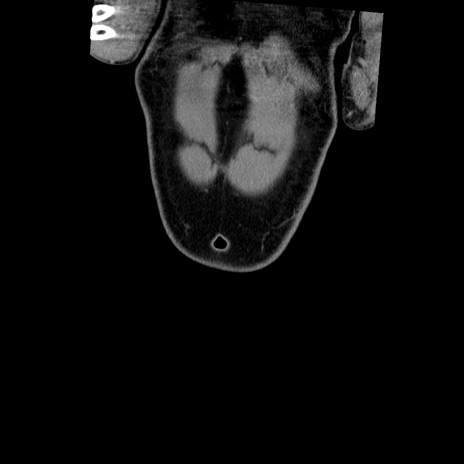

症例22(冠状断像)

横断像